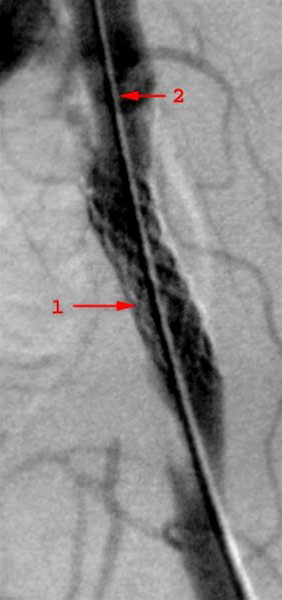

Forsnævring (stenose) i venstre bækkenarterie behandlet med stent. En Palmaz-stent (1) er indsat, som holder den forsnævrede del af pulsåren åben. Røntgenkontrast væske indsprøjtet gennem kateter (2) indført fra lysken.